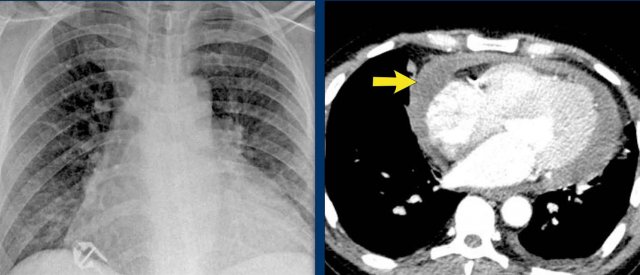

Pericardial effusion

When encountering an enlarged cardiac silhouette on chest radiography, it is essential to consider pericardial effusion as a potential mimic of cardiomegaly.

Case Example 1: Pericardial Effusion Mimicking Cardiomegaly

• On the chest radiograph, the patient appears to have a dilated heart.

• However, CT imaging clearly demonstrates that the apparent enlargement is due to significant pericardial fluid accumulation, not true myocardial chamber enlargement.

Postoperative Pericardial Hemorrhage

In patients with recent cardiac surgery, a sudden change in heart size on chest X-ray should raise suspicion for pericardial bleeding, which may be life-threatening.

Case Example 2:

• A postoperative patient showed a change in the cardiac silhouette.

• Echocardiography detected only a minimal pericardial effusion.

Case Example 2 - CT imaging

• CT imaging revealed a large posterior pericardial effusion compressing the left ventricle (blue arrow: effusion; red arrow: compressed, contrast-filled left ventricle).

• Surgical exploration confirmed a large posterior pericardial hematoma.

Note

: Minimal anterior fluid on ultrasound may underestimate the true volume if the effusion is loculated posteriorly, highlighting the value of CT in postoperative cases.